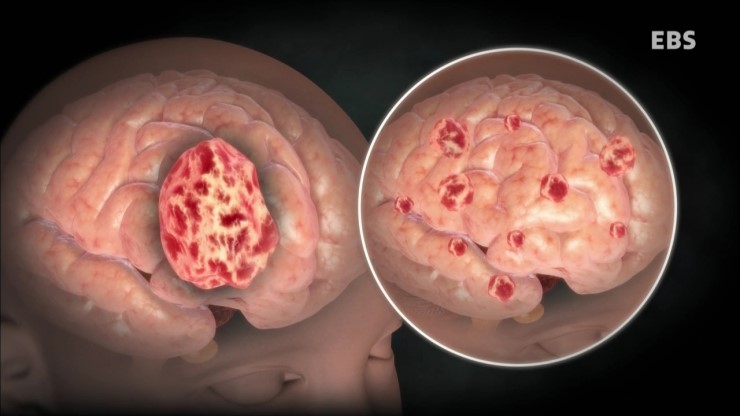

뇌종양은 뇌조직이나 뇌를 싸고 있는 막에서 발생된 종양과 머리뼈나 주변 구조물에서 멀리 떨어진 부위에서 뇌조직이나 뇌막으로 전이된 종양을 말합니다. 또, 뇌종양은 양성과 악성으로 나눌 수 있는데요. 양성 뇌종양은 성장속도가 느리고 주위 조직과의 경계가 뚜렷한 특성을 지니고 있습니다. 악성 뇌종양은 뇌암이라고도 말하며, 성장속도가 빠르고 주위 조직으로의 침투 능력이 강하여 주변의 정상 뇌조직을 빠른 속도로 파괴합니다.